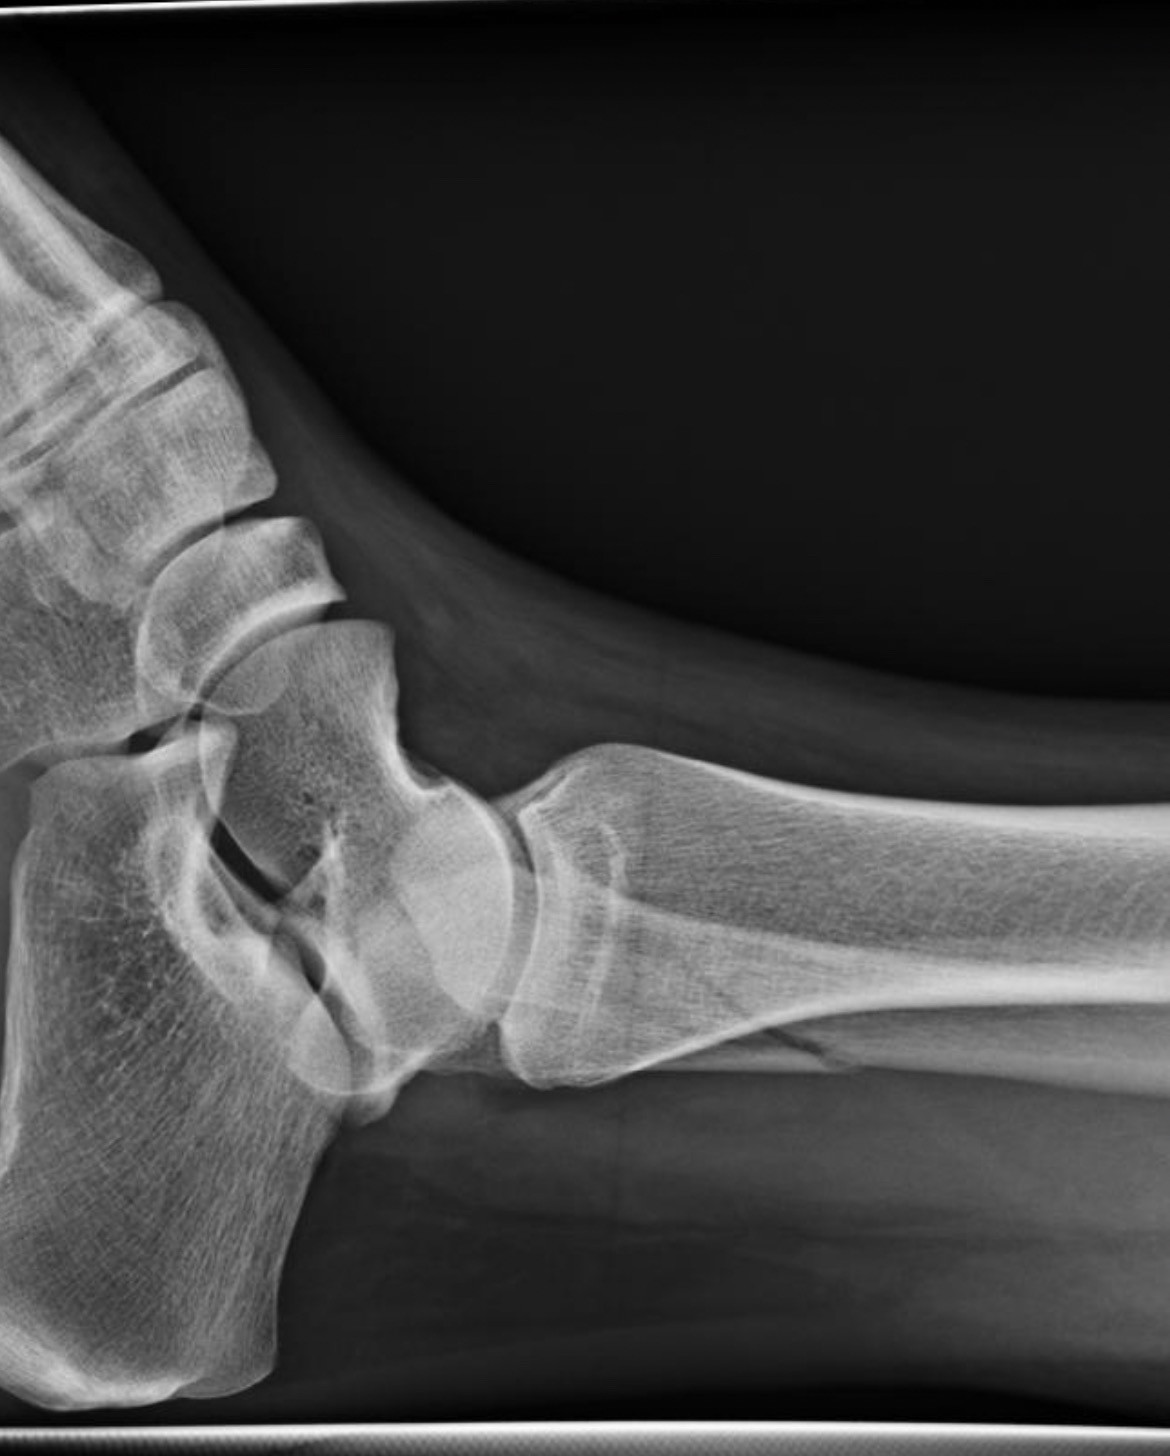

My name is Jaimie and I’m a single mother of two boys. I was playing with my 14 year old son before bed and he ended up tackling me to the ground which caused my foot to snap back to my ankle, breaking my leg bone. My son feels really bad and has been helping me with house responsibilities and helping me up and down the stairs.